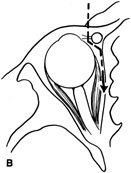

Figure 10. A. Large, well-encapsulated intraconal mass on MR scan. B. Small lateral canthotomy incision will be used to perform lateral orbitotomy and remove the intraconal mass.